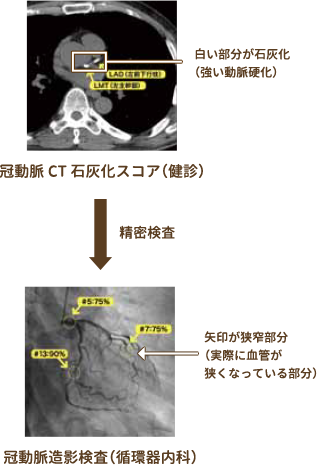

⑤冠動脈CT石灰化スコア

心臓CTで3本の冠動脈の石灰化を調べることで、冠動脈硬化の程度や動脈硬化が進んだ状態を示すプラーク(血管壁の一部が限定的に盛り上がっている状態)が広がっているかなどが分かります。冠動脈プラークの存在は、狭心症や心筋梗塞発症の基盤になります。検査に造影剤は使用しませんので、どなたでもご利用いただけます。